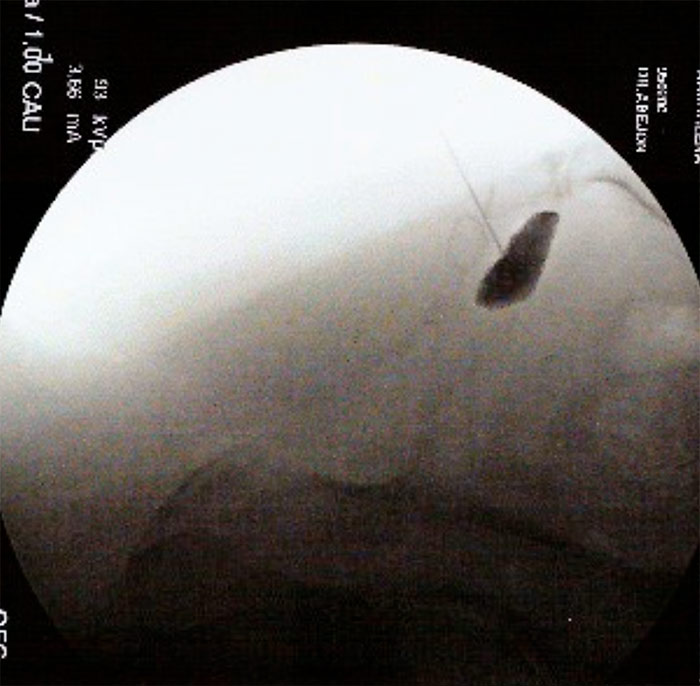

Existen diversos abordajes para realizar el bloqueo o la radiofrecuenica de esta estructira. Se describe un abordaje lateral Con el arco de fluoroscopia en posición lateral para buscar el target,  que en este abordaje es el espacio interdiscal coxigeo. En esta posición y siempre viendo el disco intercoxígeo se realiza la punción hasta atravesar atravesar el espacio interdiscal donde notaremos una pérdida de resistencia del ligamento sacrocoxigeo anterior. Se comprueba con contrste radiopáco la posición óptima de la aguja, la distribución del mismo será en la cara anterior del sacro.